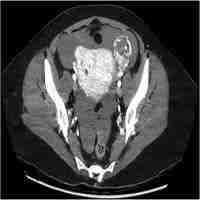

| Abstract | Tubal hydatidiform mole is an uncommon condition with about 40 confirmed cases in the accessible literature. The patient usually presents with symptoms and signs of a classical ectopic pregnancy and it is only after histological examination and DNA ploidy analysis of the conceptus that a hydatidiform mole is diagnosed. Management requires complete removal of the conceptus and follow-up needs to be arranged with an appropriate supraregional centre. The authors present a case of complete molar tubal pregnancy and a review of the literature. |